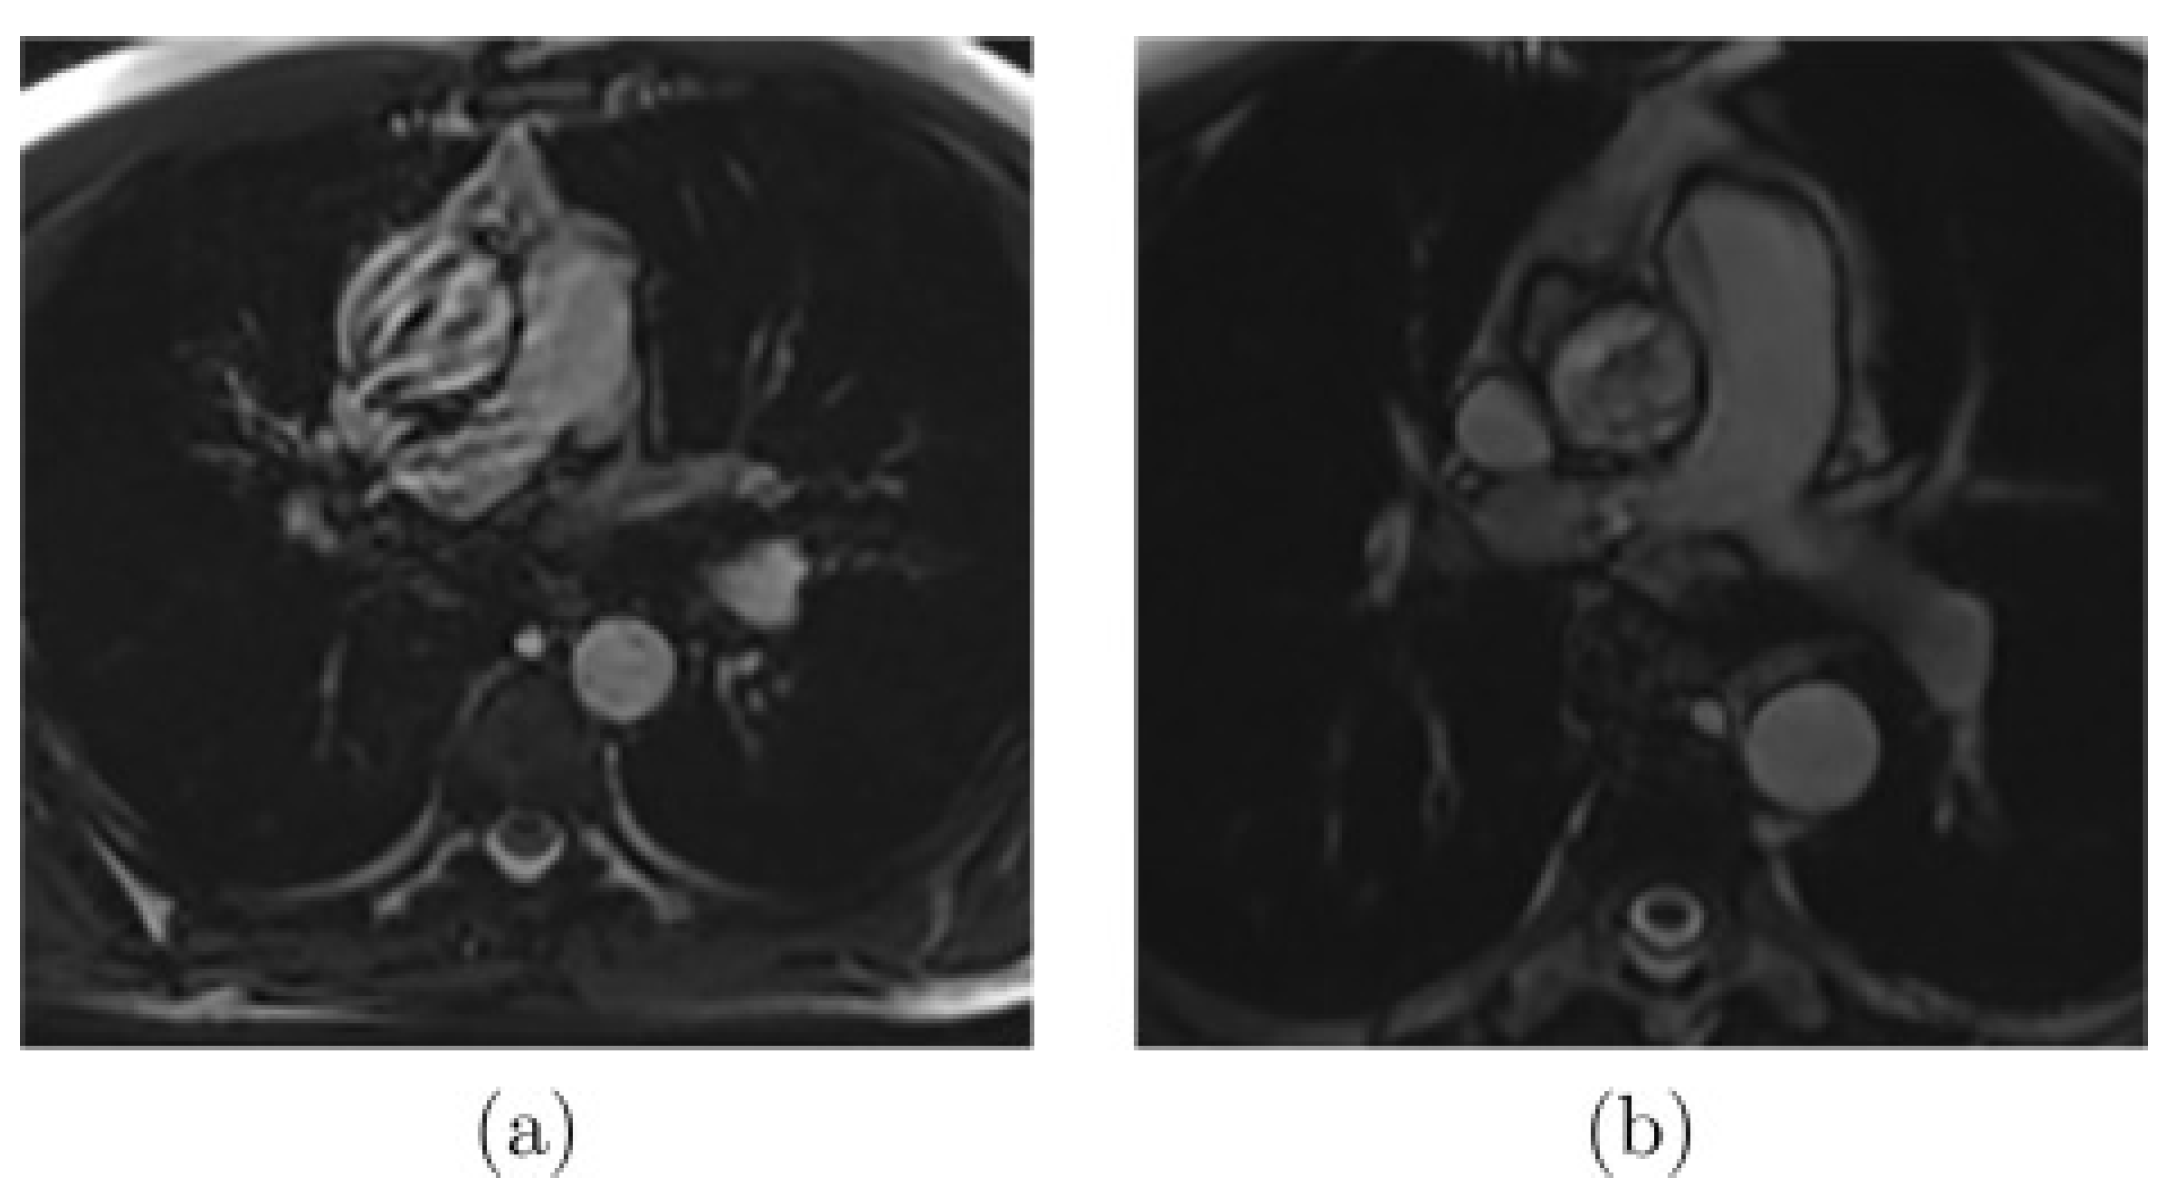

2.3.1. In-Vivo Data: Magnetic Resonance Imaging (MRI)